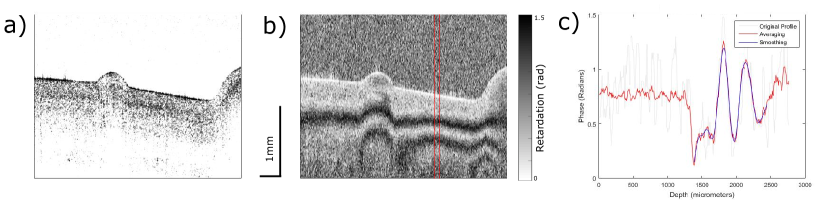

Out of the 26 samples, 10 were healthy (G0), 8 had mild degeneration (G1), and 8 had moderate degeneration (G2). All samples underwent compression using the indentation device. Since the PS-OCT setup detects orthogonal phase amplitudes we can obtain intensity (figure 2.a) and phase images (figure 2.b). The system has a π2𝜋2\frac{\pi}{2} phase wrap, the retardation gradient was calculated as the cumulative, absolute phase change divided by the depth of the smoothed profile (see method) (figure 2.c). PS-OCT images were taken in three different locations on the cartilage corresponding to three areas of interest (figure 3).

Refer to caption

Figure 2: a) Intensity image of an indented healthy (G0) cartilage sample. b) Phase image of the same sample with the averaging window indicated by the red lines. c) Phase profile showing the original, averaged, and smoothed data.